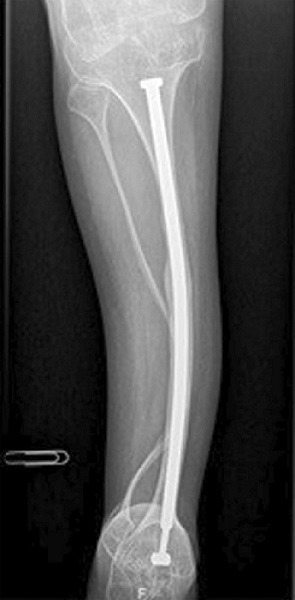

Una densitometría ósea realizada a los 15 años de edad, demostró una densidad mineral ósea lumbar (DMO) de 0,474 g/cm2 (Z-score: -6,43). Se trató con zolendronato durante una década, mejorando su DMO lumbar hasta 0,854 g/cm2. Pero, tras un año de abandonar el tratamiento, sufrió una fractura atípica diafisaria femoral, siendo entonces referido a nuestro servicio.

Se comenzó tratamiento con teriparatida subcutânea. Tras dos años de tratamiento, se detuvo la administración y se inició terapia con de-nosumab cada 6 meses, aumentando su DMO lumbar a 1,81 g/cm2 (Zscore: -0,4).